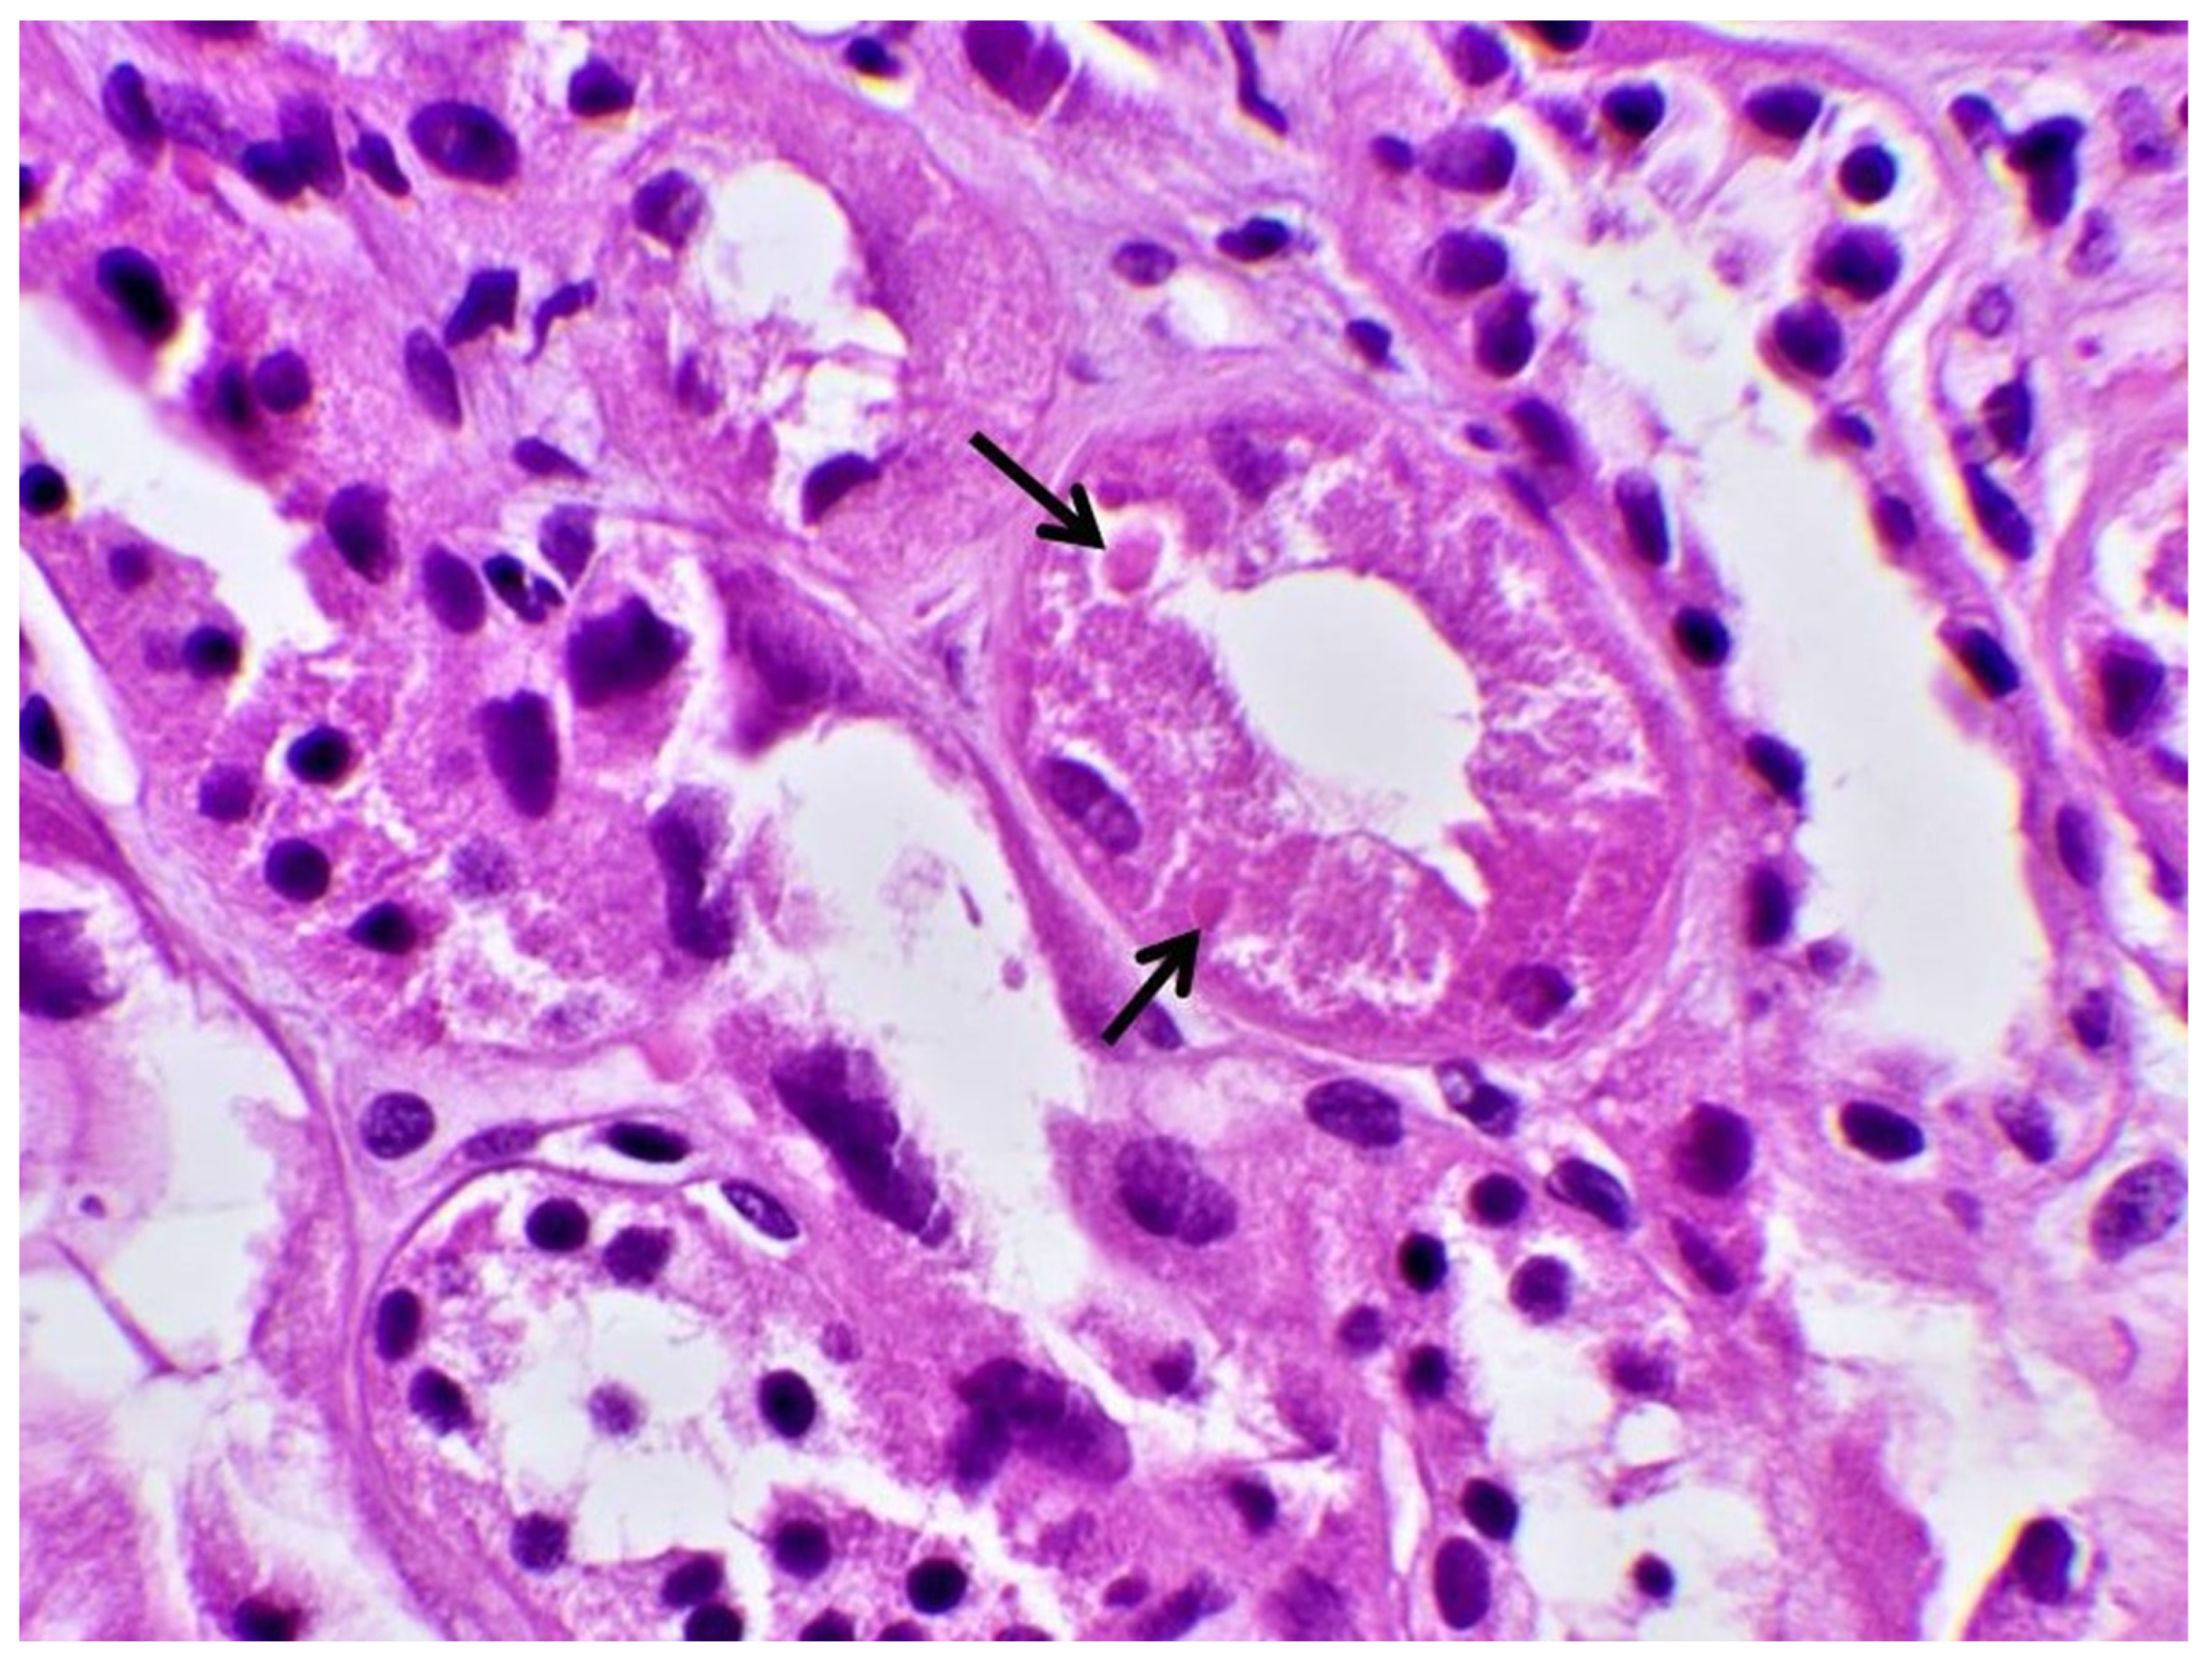

- Herlitz, L.C.; Mohan, S.; Stokes, M.B.; Radhakrishnan, J.; D’Agati, V.D.; Markowitz, G.S. Tenofovir nephrotoxicity: Acute tubular necrosis with distinctive clinical, pathological, and mitochondrial abnormalities. Kidney Int. 2010, 78, 1171–1177. [Google Scholar] [CrossRef] [PubMed]

| Biopsy | Proximal Tubular Injury | Not performed | Not performed | Not performed | Proximal Tubular Injury |